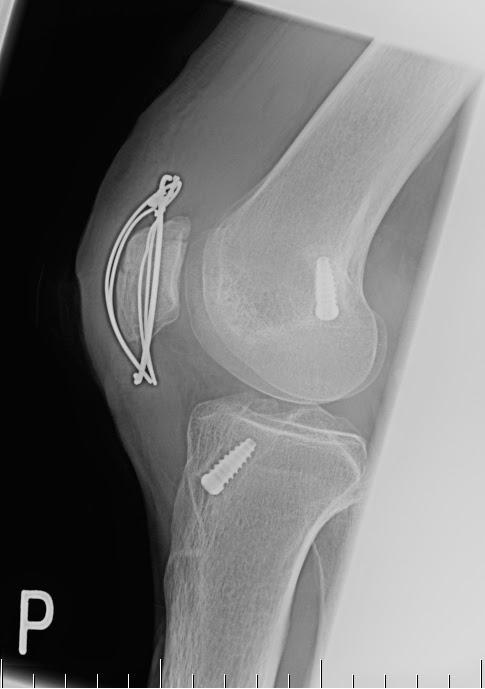

| Najděte „chybu“… |

21. 10. 2013 někdy večer Kloužu po Národní třídě a nebržděně dopadám na pravé koleno (ano, to, kde jsem si v březnu přerval ACL). Cesta na pohotovost do ÚVN (tramvají), Dg: Fr. Patellae l dx disl minim.

24. 10. 2013 někdy před den Rentgen. Vlastní snímky jsem sice v tom okamžiku neviděl, ale z internetu jsem si udělal docela představu.